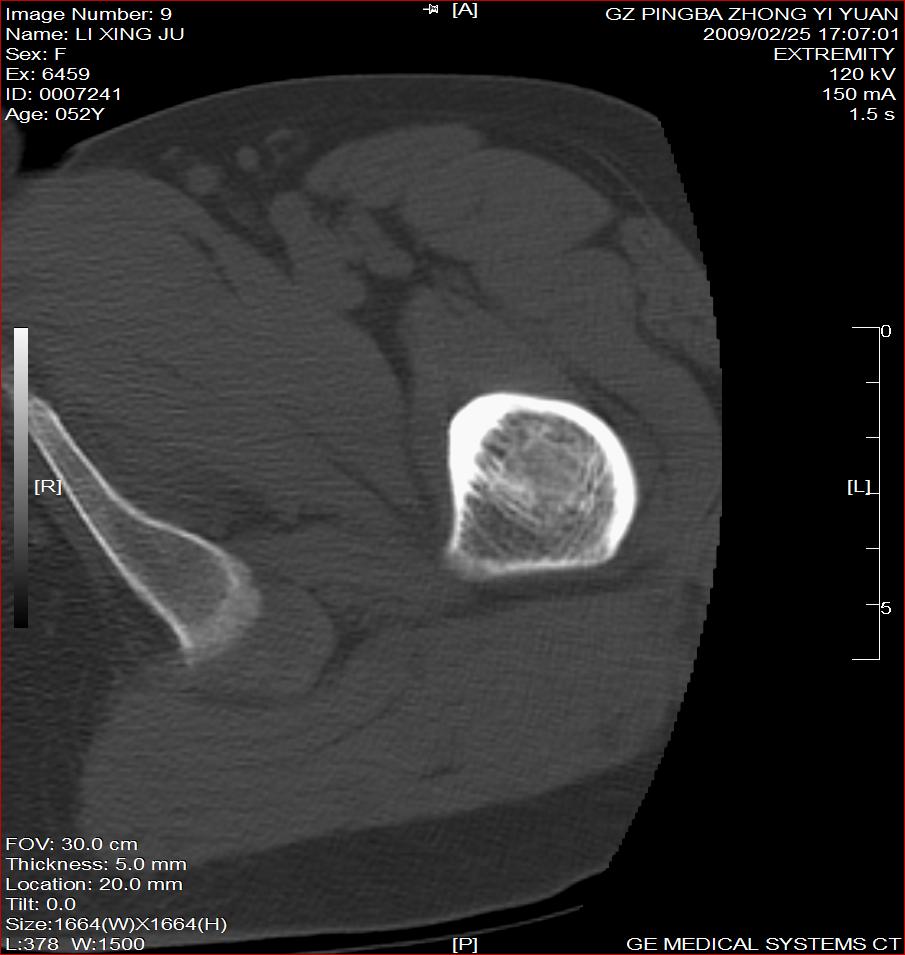

标题: CT18521:左大腿疼痛不适1+月 [打印本页]

标题: CT18521:左大腿疼痛不适1+月

考虑-----股骨骨化性纤维瘤可能性大,不除外---局限性骨纤

考虑:左股骨骨化性纤维瘤

考虑:骨纤或骨梗可能性大

考虑 左股骨骨化性纤维瘤。

骨梗塞

考虑骨化性纤维瘤可能性大